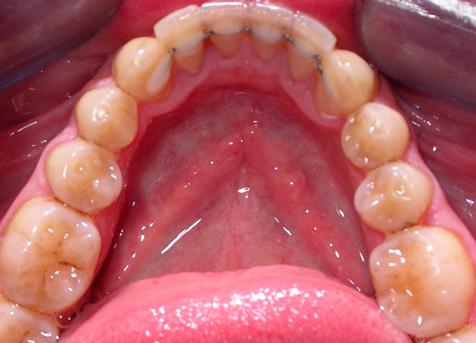

Пациент обратился с диагнозом индивидуальная макродентия.

Диагностика дополнительно выявила:- тенденцию к формированию мезиальной окклюзии,

- сужение и укорочение зубных рядов,

- ретрузию верхних центральных резцов,

- мезиальное смещение боковых отделов нижнего зубного ряда,

- ретрузию нижних резцов,

- множественные аномалии положения зубов.

Лечение проводилось с апроксимальной сепарацией эмали зубов. Применялись керамические брекеты.